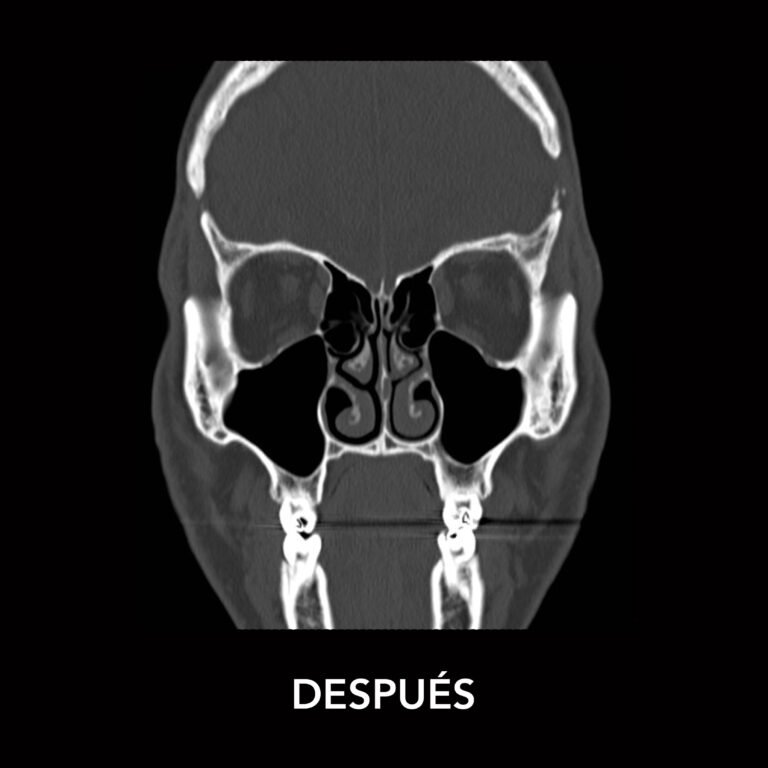

Fractura nasal o de nariz

Es una lesión en los huesos de la nariz causada por un golpe o caída, que puede provocar dolor, sangrado, deformidad y dificultad para respirar.

¿Cómo se trata?

El tratamiento depende del tipo de fractura:

• Reducción cerrada: reposicionamiento manual de los huesos sin cirugía si la lesión es reciente.

• Cirugía: se corrige la estructura nasal cuando la fractura es más compleja o afecta la respiración.